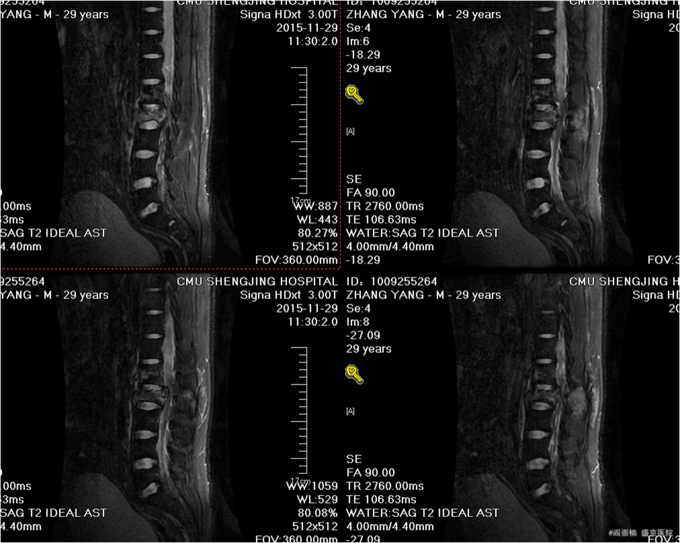

1.患者,青年男性,29岁,以“摔伤后腰部疼痛活动受限8小时”为主诉入院。 2.现病史:患者及家属述于2015-11-29晚2点左右奔跑过程中不慎摔倒,伤后意识稍有不清,唤之能醒,急送至我院急诊,行相关CT检查,提示腰2椎体及附件爆裂骨折,脊髓受压;腰1椎体、左侧横突骨折;骶1隐裂,我科以“腰椎骨折”为主要诊断收入院。患者病来无头晕头痛,无恶心呕吐,无腹痛腹泻,未排便排气.

专科查体:腰2椎体深压痛,叩击痛,双侧屈髋肌力4级,屈膝肌力5级,伸膝肌力5级,双足足趾肌力(L5,R5),左大腿内侧痛觉稍减弱,膝关节以下皮肤感觉正常,双侧足背动脉搏动可触及,末梢血运良好。 辅助检查:腰椎CT(2015-11-29):腰2椎体及附件爆裂骨折,脊髓受压;腰1椎体、左侧横突骨折;骶1隐裂